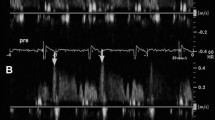

The AngioPlus system (Pulse Medical Imaging Technology, Shanghai, China) was used to calculate the QFR. We chose two planar angiographies close to the standard position and eliminated collateral interference, and the separation between the two planes was at least 25°. The three-dimensional reconstruction of the angiographic results was performed using the AngioPlus system. The software computed the following two QFR pullbacks: (a) fQFR pullback, a fixed empiric hyperemic flow velocity of 0.35 m/s derived from previous FFR studies was used for computation; and (b) cQFR pullback, a frame count analysis performed without pharmacologically-induced hyperemia and the modeled hyperemic flow velocity, which was derived according to the frame count used for computation [8]. The calculation of QFR was performed independently by two experienced operators who were blinded to the clinical grouping.

At the end of CAG, IMR was measured in patients with CSX with a thermodilution technique as described previously [9]. Briefly, the aortic pressure transducer was zeroed to air, and after routine preparation and calibration, the pressure wire was introduced in the guide catheter and positioned with the wire sensor at the guide tip for electronic equalization. The pressure wire was advanced to the distal part of the coronary artery (approximately two-thirds of the vessel). After intracoronary injection of 250 mg of isosorbide dinitrate, the following parameters were measured, both at baseline and after hyperemia was induced with intravenous infusion of adenosine at a rate of 140 mg/kg/min: (1) mean aortic pressure, (2) mean distal pressure, and (3) mean transit time. The mean transit time was calculated as the average of three transit time measurements during three separate injections of 3 ml 0.9% saline at room temperature. IMR was then calculated as the mean distal pressure at hyperemia multiplied by the mean transit time at hyperemia. Equally, the calculation of IMR was also performed independently by two experienced operators who were blinded to the clinical grouping.

No significant difference in the baseline cQFR between the two groups was observed (P = 0.492). The cQFR of the experimental group increased significantly after RIPC (Fig. 1), and no significant difference was observed compared to the control group (P > 0.05) (Fig. 2). The cQFR changes in the experimental group were larger than those in the control group (P < 0.001). Further analysis revealed that in the RIPC group, the cQFR change in the UL subgroups was lower than that in the LL subgroups (Table 3).